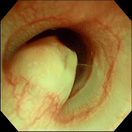

気管虚脱

気管支腫瘍

気管腫瘍

喉頭腫瘍

鼻腔内腫瘍(犬)

鼻腔内腫瘍(猫)